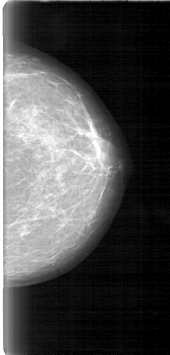

D_4017_1.LEFT_CC

LEFT_CC LINES 5311 PIXELS_PER_LINE 2536 BITS_PER_PIXEL 12 RESOLUTION 43.5 NON_OVERLAY